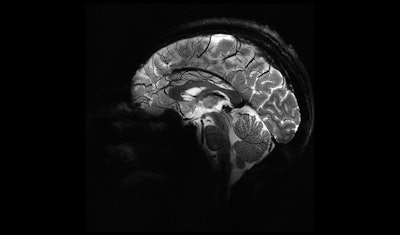

Sagittal view of the brain at 11.7 tesla makes it possible to visualize the cerebellum in very fine detail.